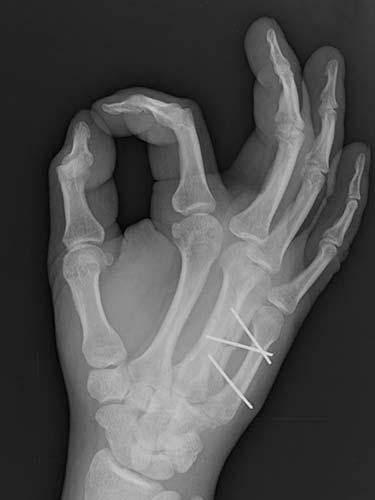

31 year old that suffered a broken bone in his hand while at work. Attempts were not possible at treating the patient without surgery because of the need to use his hand to help out with family obligations. He chose to have the hand treated with temporary wires that allowed him to help out with family obligations. The patient healed without any problems having regained full use of his hand.

- After